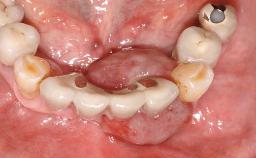

Surgical treatment of a 68-year-old female patient with a distal extension situation in the left mandible. As the CBCT analysis reveals, the bone crest anatomy in the area is not ideal and necessitates an augmentation procedure to achieve a good long-term prognosis for the planned implants and their prostheses.

For soft tissue management, the initial healing caps are replaced with a longer type 8 weeks after implant placement in a second intervention before prosthodontic treatment is initiated.